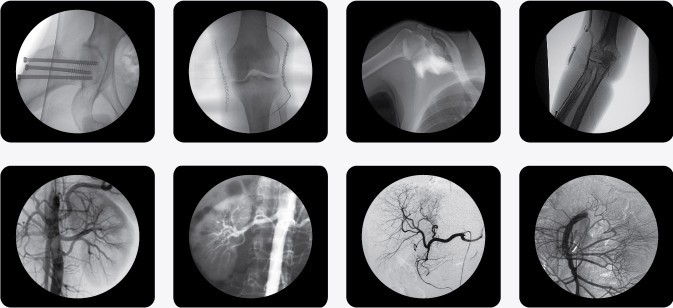

一、C型臂X光機PLX7000B的用途

廣泛應用于 介入科、骨科、外科、矯形外科、泌尿外科、脊柱外科、腹部外科、疼痛科、心臟科、消化科、婦科及手術室等。

三、C型臂X光機PLX7000B數(shù)字高清影像,支持您做出精確診斷

·數(shù)字化高頻發(fā)生器,采用微焦點,確保精準的射線劑量控制,滿足您的多種復雜臨床診治要求。

·球館大熱容設計,保證設備持久工作能力,伴隨您一同應對各種復雜手術。

·全數(shù)字化百萬像素影像采集系統(tǒng),優(yōu)化設計和配置,為您提供高分辨率、高灰階圖像,支持您做出精確診斷。